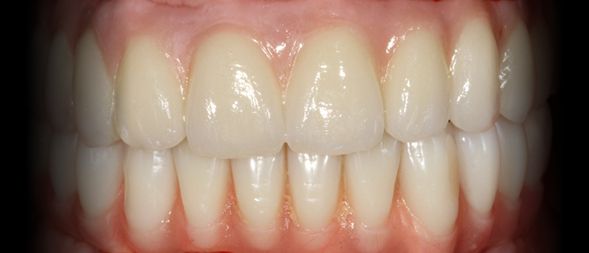

Caso clínico sobre Estética Dentária